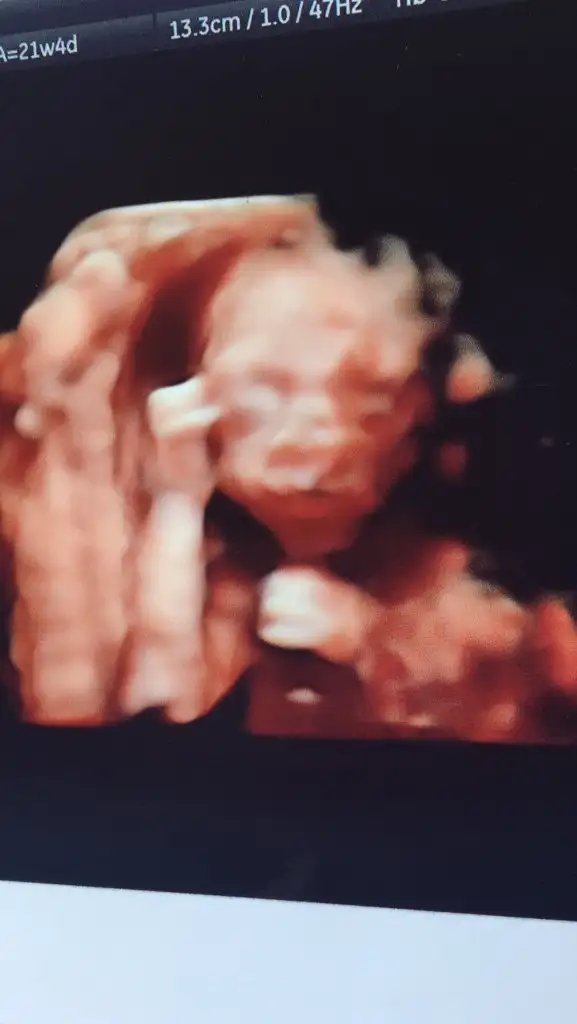

maşallah tekrar kuzumevet teyzeler biz dün detaylı usg ye girdik.

çok şükür gelişimi organları herşeyi olması gerektiği gibi çıktı oğlumuzun :)

erkek oldugu zaten kesindi iyice kesinleşti sağolsun doktorumuz pipi ucuna kdr gösterdi

biraz inatçı olcak gibi dedi doktorrr hep kıpır kıpırdı yine.

doktor görmek için bastırıyo oda içerden tekme atıyo

rahatsız oldu heralde

boyumuz 25 cm kg 420 gram cıktı.

cumartesi günüde 22+1 de şeker yüklemesi yapılıcak.

bunlarda yakalayabildiğimiz resimlerimiz :)

Oyyyy çok tatlı yaa maşallah kuzuyaevet teyzeler biz dün detaylı usg ye girdik.